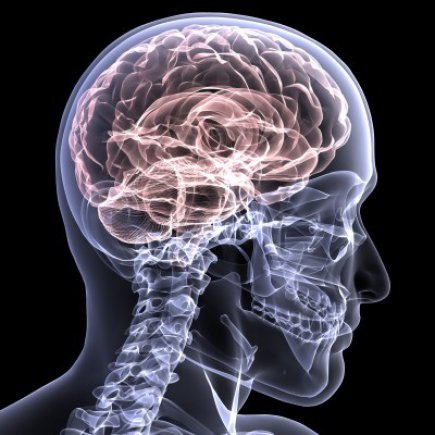

뇌의 혈관이 막혀 해당 영역의 뇌 일부가 죽는 상태입니다. 뇌혈전증과 뇌색전증이 있습니다. 심한 협착으로 인해 뇌로 가는 혈관이 완전히 막히거나 혈류가 현저히 감소하면 뇌 조직의 이 부분이 죽고 결국 녹습니다. 뇌연화증은 뇌세포가 죽어 부드러워지는 현상이고, 뇌성마비는 뇌경색으로 인해 뇌세포가 죽어가는 현상이다. 요약하자면 뇌혈관이 막혀 눈앞의 뇌조직이 괴사하는 질환이다.

뇌혈관이 막혀 뇌의 일부가 파괴되는 질환이다. 심장병이나 동맥 경화로 인해 발생할 수 있으며 이는 60세 이상의 사람들에게 더 흔합니다. 고혈압, 고지혈증, 당뇨병이 있는 사람들은 동반 증상을 경험할 수 있지만 날씨가 추울 때 노인들에게 더 흔합니다. 뇌의 특정 부위에 흔히 발생하며 한쪽 팔과 한쪽 다리의 마비가 뇌경색의 대표적인 증상이다.